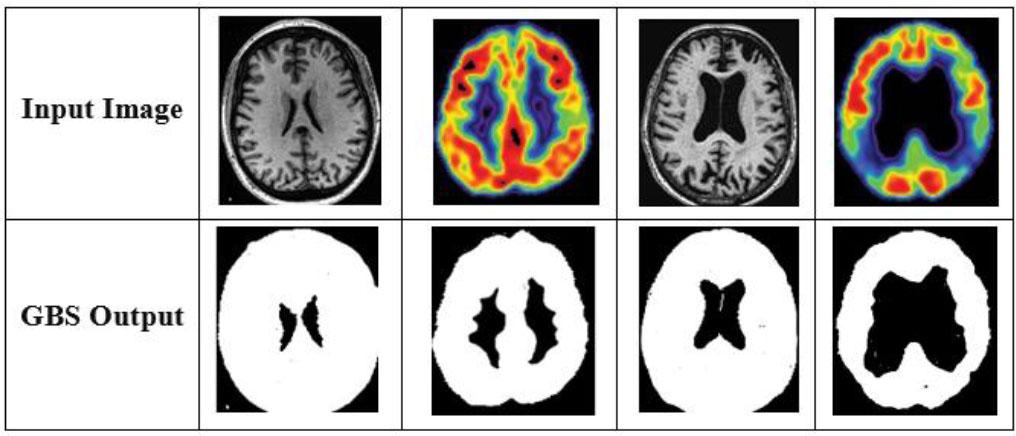

The abnormal region is segmented using the GBS model [30] to specifically detect the region for early diagnosis of AD. GBS is a technique for segmenting images to enhance their quality by using graphs. Here, E is the set of edges composed of two vertices (vi, vj), G = (V, E) is an undirected graph, and wij is edge weight. Edge weights in GBS indicate the degree of dissimilarity between two pixels in an image.

Visual examples of segmented regions.

In the GBS model, k serves as a control-scale parameter that influences the preference for merging components. Specifically, this threshold determines the minimum dissimilarity required between two regions for a boundary to be established. A higher k value promotes the formation of larger and more coherent segments by allowing greater intra-region variation before splitting occurs. This technique is particularly important for accurately describing pathological regions in brain images, where preserving structural consistency is essential for reliable disease localization and diagnosis.